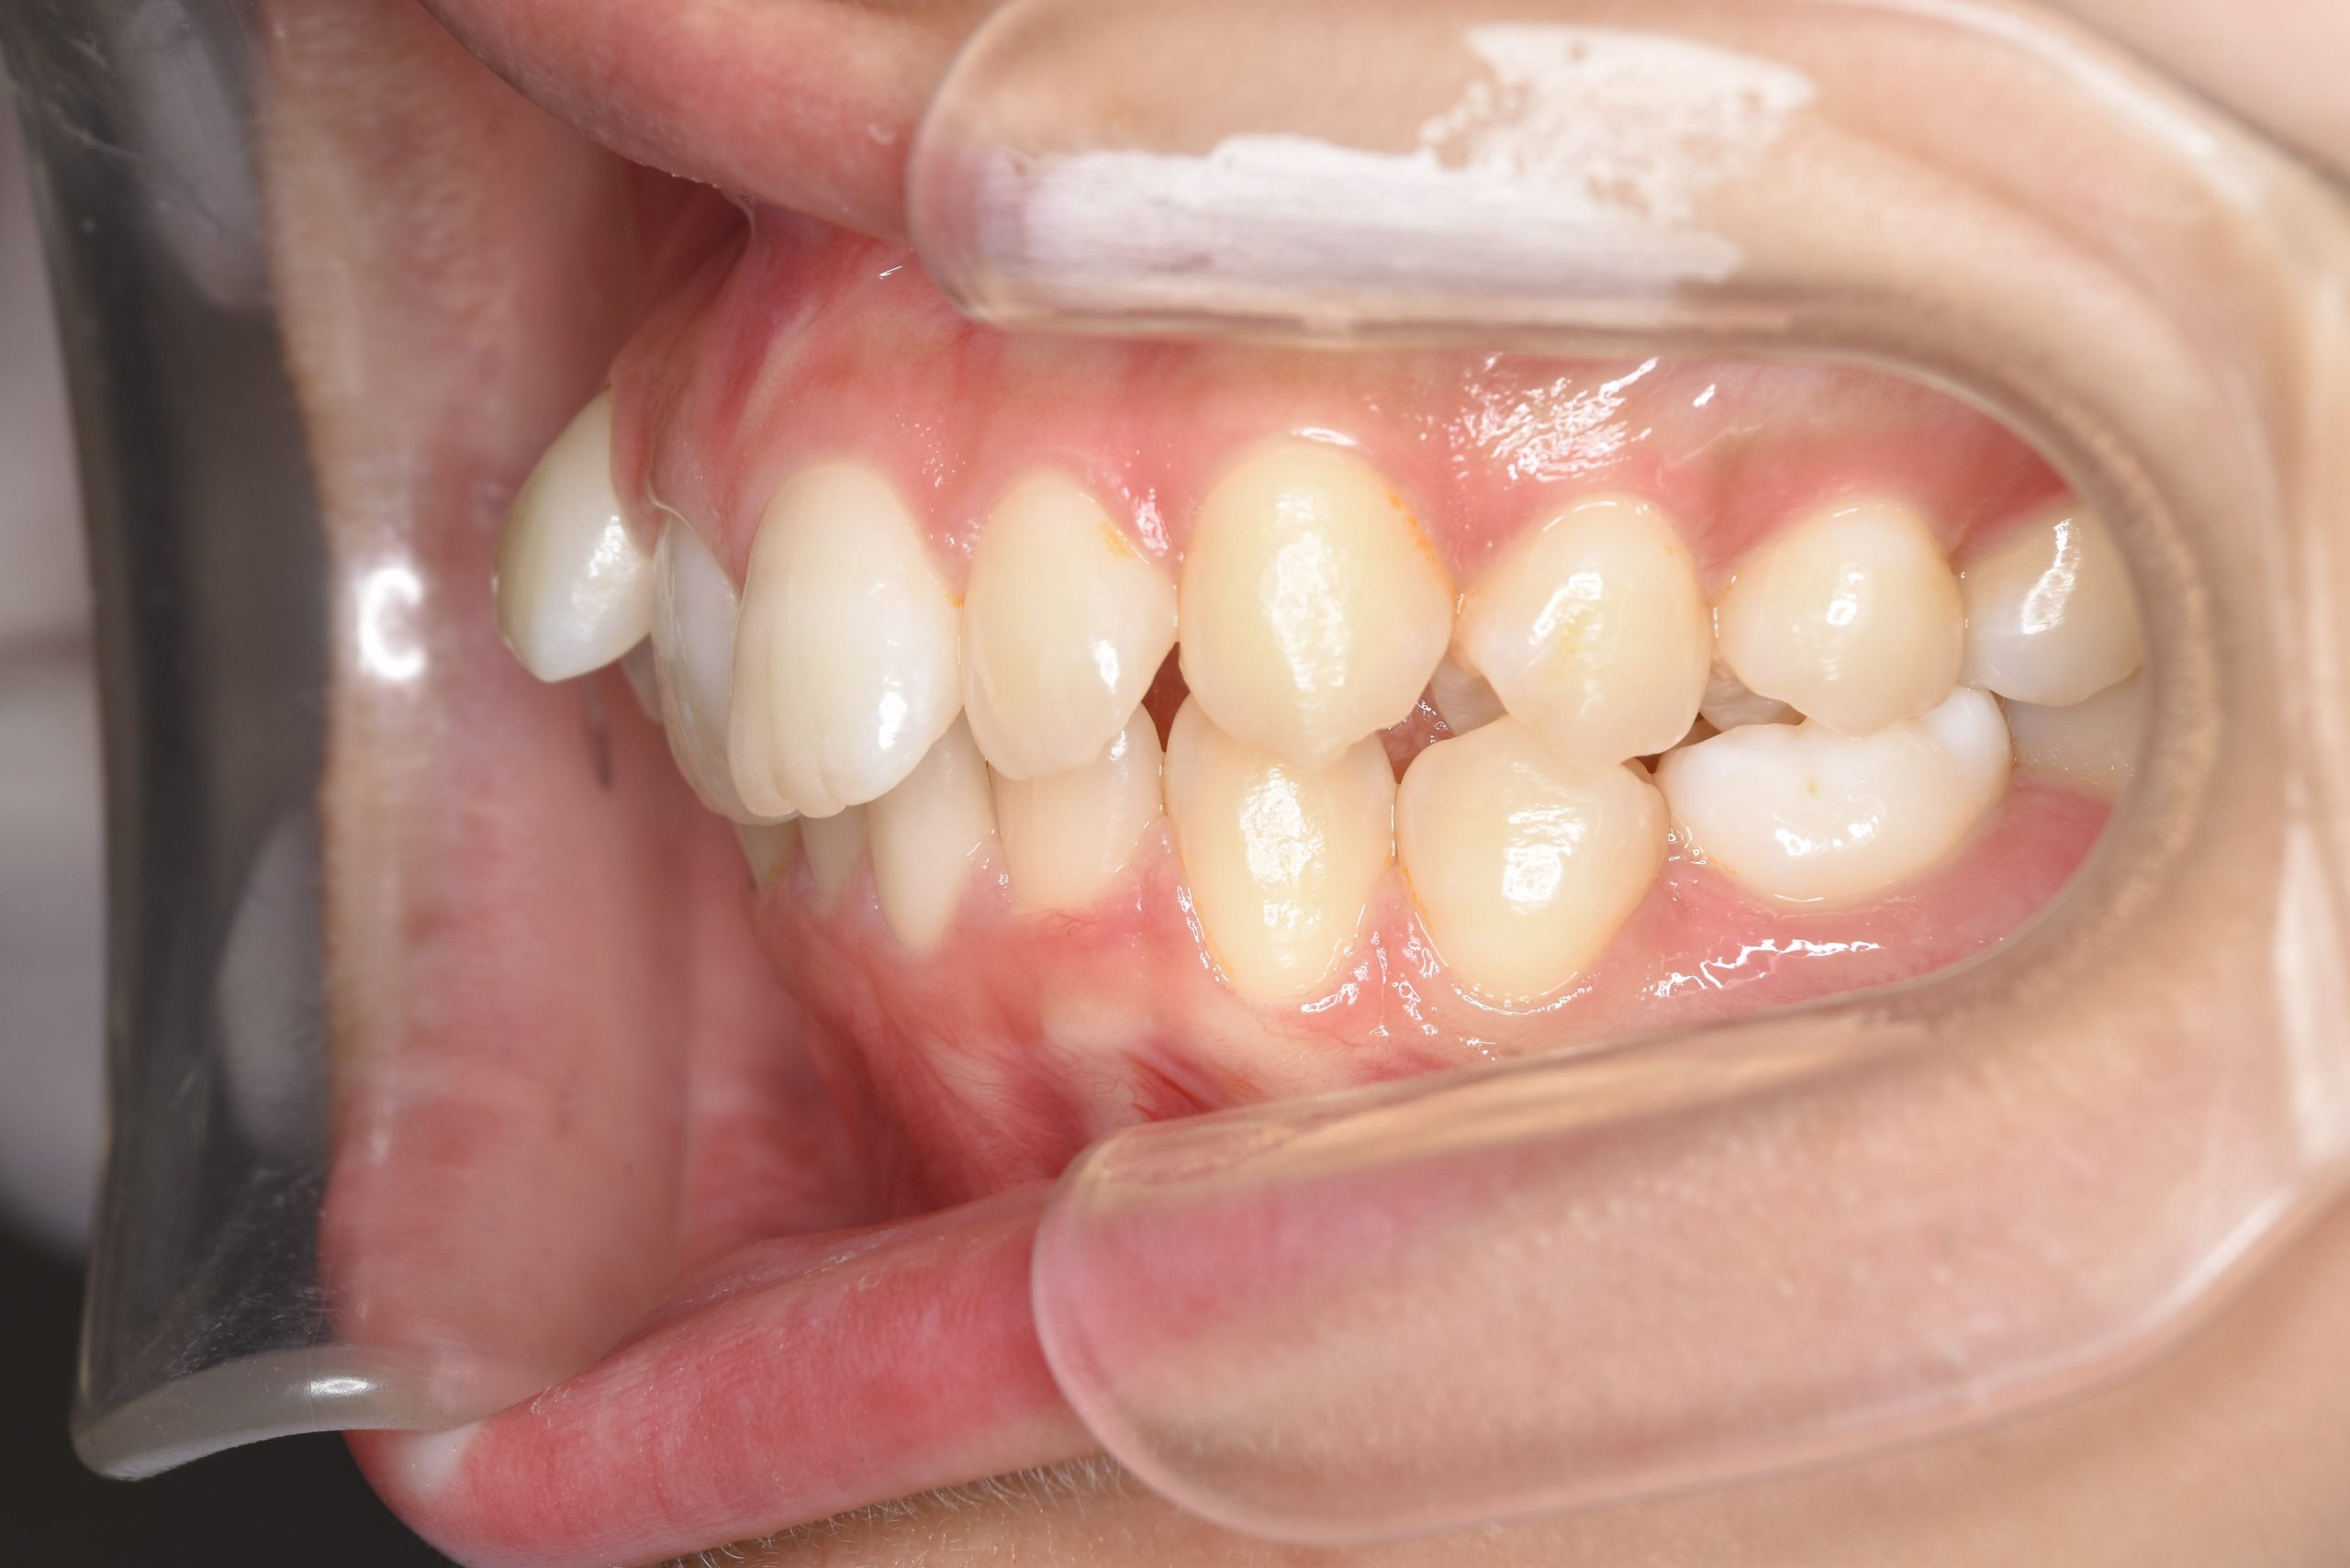

ビフォー

全顎ワイヤー矯正 症例_418

アフター

主訴 歯並びがガタガタ ※抜歯あり

施術内容 成人矯正1期治療

治癒期間 2年10か月間

費用 1,069,200円(税込)